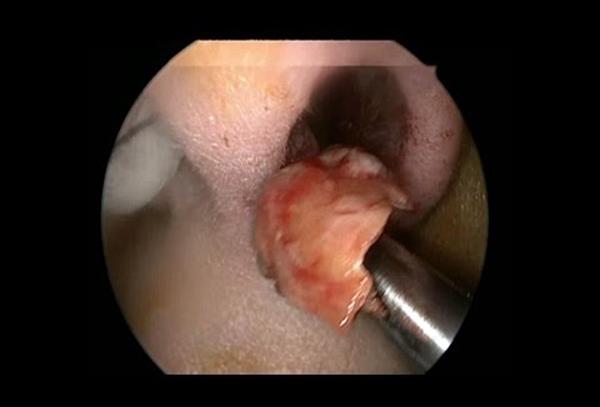

Ход операции

Эндоскопическая гайморотомия обычно выполняется при местном обезболивании, но в некоторых случаях может потребоваться общий наркоз. Перед проведением операции производится тщательное промывание носовой полости и синусов специальными антисептическими растворами. Удаление грибкового тела осуществляется с помощью эндоскопических щипцов. После удаления патологического очага гайморова пазуха повторно обрабатывается антисептическими растворами. Ход операции контролируется с помощью микрокамеры. Средняя продолжительность хирургического вмешательства составляет 20–30 минут.

Поскольку грибковое тело не проникает в слизистую оболочку гайморовой пазухи, его можно рассматривать как инородное тело. При наличии современного оборудования и опытного специалиста его успешно удаляют с помощью эндоскопического оперативного вмешательства. В настоящее время это является стандартом золотого уровня для малоинвазивной хирургии.